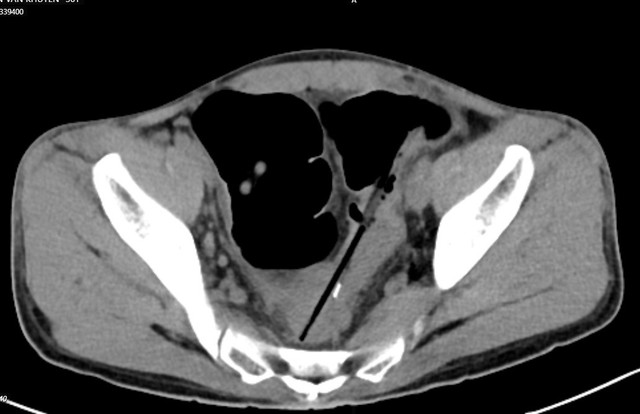

Bệnh nhân được chẩn đoán: Áp xe trong ổ bụng do thủng đại tràng sigma do dị vật, dị vật ruột non/tâm thần phân liệt. Ảnh BV

Chụp cắt lớp ổ bụng thấy hình ảnh 02 dị vật hình que đầu kim loại trong quai ruột vùng hạ vị, đâm xuyên thành ruột tạo ổ dịch khí vùng tiểu khung cạnh cơ bịt phải; Dị vật trong quai ruột hạ sườn phải; Dày thành trực tràng, đại tràng sigma và quai ruột ngang rốn; Giãn lan tỏa các quai ruột non.